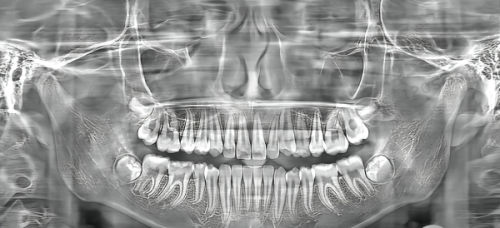

长沙牙祖口腔医院是一家集口腔医疗、预防、保健于一体的现代化口腔医疗机构。自成立以来,凭借娴熟的医疗技术、温馨的就医环境和贴心的服务,赢得了广大患者的信赖与好评。

在种植牙技术方面,长沙牙祖口腔医院实力雄厚。它主要采用即刻种植牙技术、微创种植牙技术、数字化导板种植牙技术、半/全口All - on - 4种植牙技术等。这些精良的技术能够根据患者的牙槽骨情况,为患者提供更合适的种植牙方案。

比如,如果患者的牙槽骨条件不好,但可以通过植入做半/全口种植牙,那么医生就会推荐All - on - 4种植牙技术。如果患者想要当天拔牙当天种植来修复门牙,且牙槽骨条件符合的情况下,就会使用即刻种植牙技术。

医院的种植牙医生都是拥有多年临床经验的实力医生,像周磊院长、陆益兰院长等,他们都有着不错的口碑和技术,能够根据患者的牙槽骨情况来预算制定种牙方案,价格不贵还适合患者自己。

在牙齿矫正方面,也有特别多非凡的医生,比如陈剑阳医生、吕波医生、付丽群医生等。他们能够针对不同的情况制定合适的矫正方案。医院还拥有叙利亚外籍医生沙米,他可以和顾客进行中文沟通,各类矫正器都可以做,不挑正畸品牌,矫正技术好,深受年轻患者的喜爱。